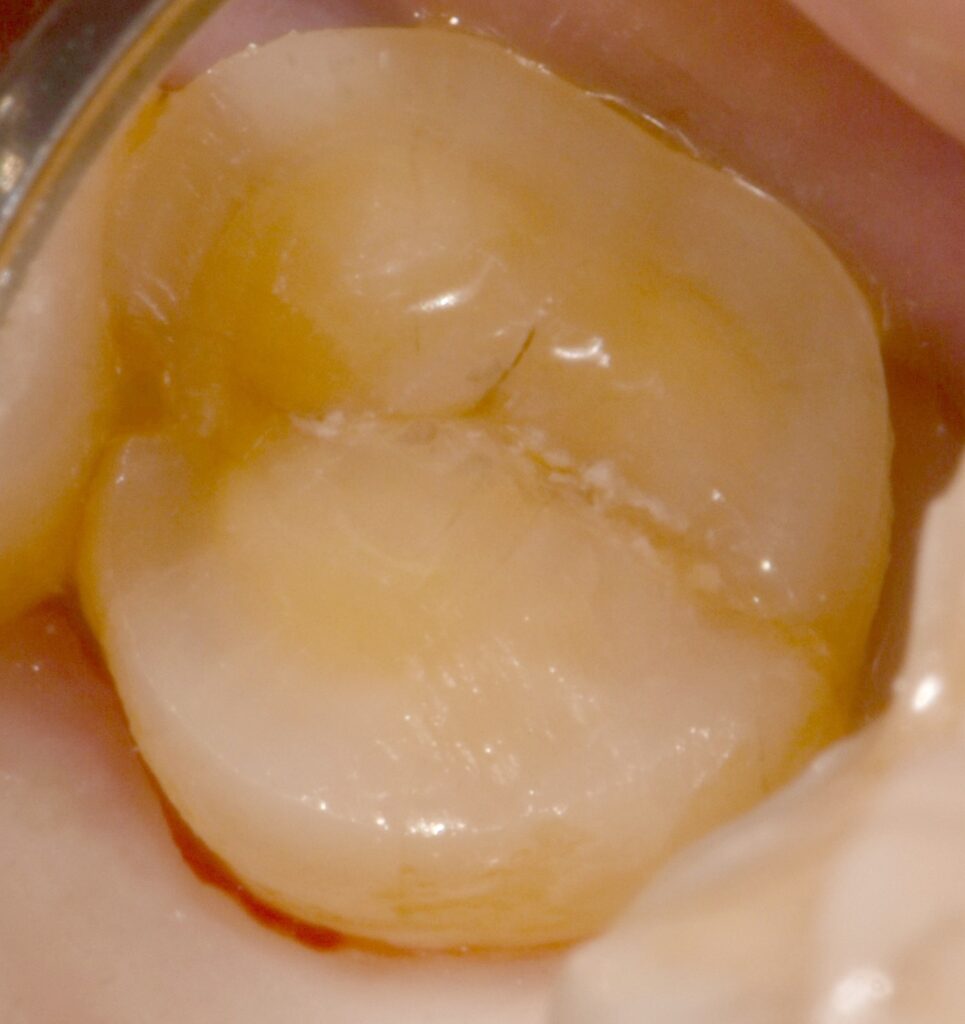

기존에 다니시던 환자분이 정기검진으로 내원하셨고, 기존 인레이 주변에서 특별한 통증이나 증상이 없었지만 이차충치가 발견되었습니다.

그냥 육안으로 봤을 때는 아무런 문제가 없어보입니다.(좌측 사진)

하지만 큐레이(Q ray) 장비를 이용하면 이렇게 기존 인레이에 이차우식이 생겼음을 명확하게 확인할 수가 있습니다.(우측 사진)

​만약 위의 상황에서 인레이 하방의 이차우식을 조기에 발견하지 못한 채로 오랜 시간이 지났다면 어떻게 되었을까요? 아마 충치가 깊게 진행되어 신경치료를 해야 하는 상황에 이르게 되었을 수도 있었을 겁니다. 조기에 정확한 진단을 통해 문제를 더 크게 만들지 않았던 좋은 사례였습니다.